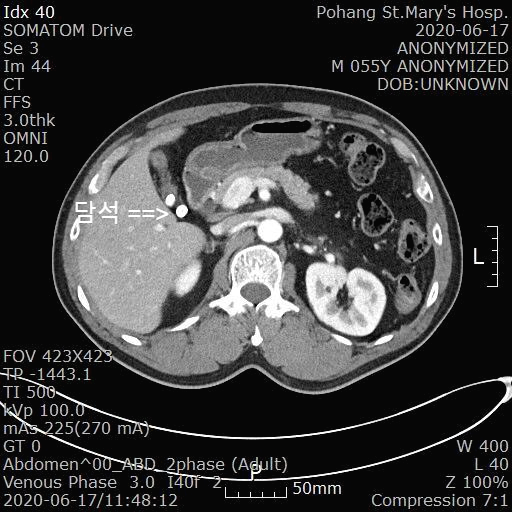

그래서 혹시 담낭 관련 질환은 아닐까 의심하고 복부 CT를 시행했습니다.

[복부 CT 판독 소견]

A few GB stones and GB wall thickening

---> Chronic calculous cholecystitis, suggested

복부 CT에서 담낭에 2개의 담석이 보이면서 담낭벽이 두꺼워진 만성 담석 담낭염(Chronic calculous cholecystitis)으로 진단되었습니다.